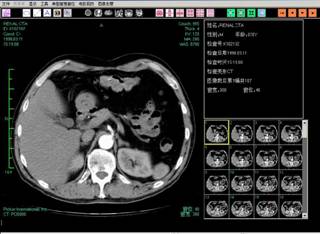

实验室近年来在计算机视觉、图像处理与智能分析方面开展深入研究,聚焦于人工标注“小、弱、少”场景下的图像自动检测、分类等核心计算机视觉任务,设计了多种新颖的半监督、跨领域自适应深度学习方法,相关技术在国际上处于领先水平。多篇研究成果发表在人工智能领域著名国际期刊IEEE JBHI、Artificial Intelligence in Medicine、智能医学影像分析国际顶级会议 MICCAI'2021等。